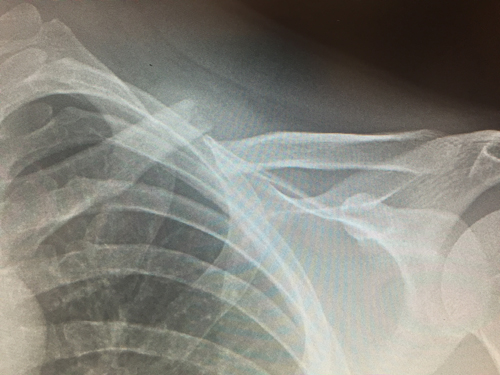

Clavicle Fracture

Fractures are typically a result of a fall onto the shoulder with most occurring in the mid shaft of the bone.

Diagnosis is made using x-rays but can be supplemented with a CT scan for more complex fractures being considered for surgical repair.